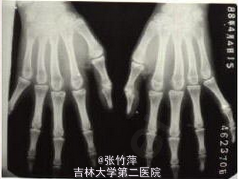

查体:患者明显外形异常。四肢细长,蜘蛛指,双臂平伸指距大于身长,双手下垂过膝,下半身比上半身长。长头畸形、面窄、高腭弓、耳大且低位。皮下脂肪少,肌肉不发达,肌张力低,呈无力型体质。脊柱侧凸。 辅查: 胸片如图一,示脊柱侧突 手部X片如图二,示蜘蛛指 手部外形如图三 右眼视力为 0.25,左眼为 0.05,双眼眼压正常;瞳孔散大后裂隙灯检查发现双眼晶状体脱位入玻璃体腔,眼底检查发现存在视网膜变性,但是未见视网膜撕裂及视网膜脱离的任何迹象。